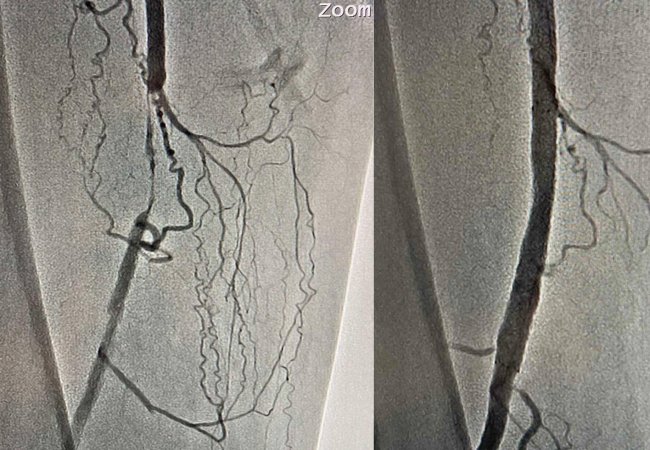

Медики вирішили провести дослідження судин (ангіографію) ураженої кінцівки, у ході якої виявили порушення кровотоку у стегновій артерії.

Врятувати ногу чоловіку можна було лише провівши стентування. Команда судинних хірургів на чолі з Олександром Голубом успішно виконала малоінвазивне оперативне втручання з відновлення кровопостачання.

Стент був встановлений усього через один прокол. Це дозволило пацієнту вже наступного дня вільно ходити коридорами лікарні. А через три дні поїхати додому.

Результат проведеної операції ви також можете бачити на зображеннях артерій, зроблених після завершенню стентування.